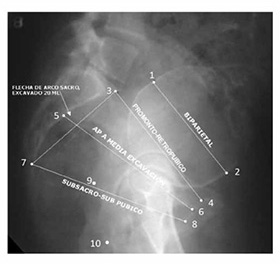

Es la medición de los diámetros de la pelvis ósea, y puede ser externa e interna.

Esta medida nos da el denominado conjugado externo de Baudelocque que puede medirse con la paciente de pie, y a su valor normal (19 a 20 cm) se le restan 8,5 a 9,5 cm de partes blandas y óseas. De esta forma puede deducirse el valor del promontopúbico mínimo. Las otras medidas serian la distancia del diámetro biespinoso (24cm) y la distancia entre ambas crestas iliacas (28cm) y el diámetro bitrocantéreo, cuyo valor normal es de 32 cm. A la pelvimetría interna le corresponde medir el conjugado obstétrico calculando a través del tacto vaginal el conjugado diagonal, al medir la distancia que media entre el dedo explorador que se pone en contacto con el borde inferior de la sínfisis y la punta del dedo que toca el promontorio.

El conjugado obstétrico es de 1,5 cm menos que la distancia del CD. En el estrecho inferior debe evaluarse el diámetro biisquiático. El diámetro anteroposterior de este estrecho se mide tomando la distancia entre el cóccix y el punto inferior de la sínfisis del pubis, y por último, en este estrecho inferior se debe explorar el ángulo que forman entre si las dos ramas isquiopubianas y el ángulo pubiano, que es muy agudo en la pelvis masculina, obtuso en la pelvis plana y recto en la pelvis femenina.